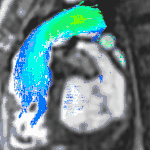

4D flow CMR

Conventional phase contrast imaging can be extended by applying flow-sensitive gradients in 3 orthogonal planes within a 3D volume throughout the cardiac cycle. Such 4D imaging encodes the velocity of flowing blood at each voxel in the volume enabling fluid dynamics to be visualised using specialist software. Applications are in complex congenital heart disease and for research into cardiovascular flow characteristics - however it is not in routine clinical use due to the complexity of post-processing and relatively long acquisition times.[25]